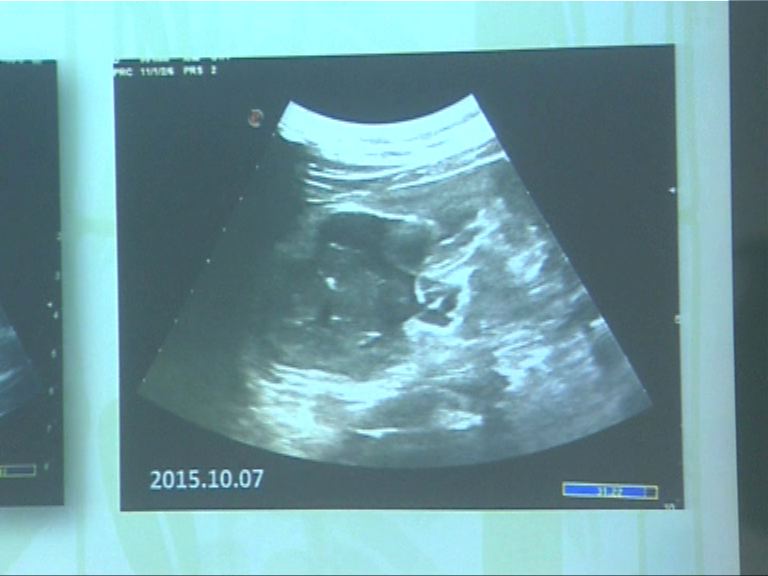

【now新聞台】海洋公園宣布大熊貓盈盈流產,園方今早再為盈盈照超聲波時,發現胎兒身體結構變得模糊,部分組織被母體吸收。專家指暫時未知流產原因,但排除是環境因素影響。

在休息室的盈盈攬着竹葉,看起來精神不錯,但海洋公園的專家已經證實牠肚裏的嬰兒已經流產,胎兒部分組織正被母體吸收。

海洋公園的專家是在星期二為盈盈照超聲波時發現胎兒有異常,至於為何會流產,仍然是個謎。